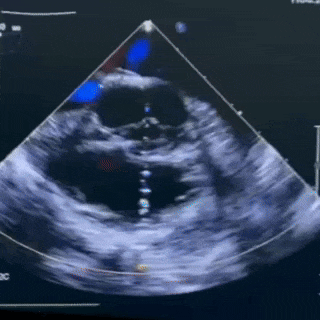

超声描述:

1.心脏各房室内径基本正常。

2.室壁回声、厚度正常,运动未见明显异常。

3.房间隔回声未见明显连续中断。CDFI:房水平未见明显过隔分流信号。

4.室间隔室上嵴回声连续中断。CDFI:室水平见收缩期高速左至右过隔分流信号,束宽约2.9mm,CW:4.21m/s ,PG:71mmHg。

5.各瓣膜回声、形态、活动未见明显异常。CDFI:二三尖瓣反流轻微;肺动脉瓣反流轻微。

6.主肺动脉内径基本正常。

7.主动脉弓降部位置、形态未见明显异常。左颈总动脉与头臂干共同开口于主动脉弓。

超声诊断:

先天性心脏病

室间隔缺损

左颈总动脉与头臂干共同开口于主动脉弓